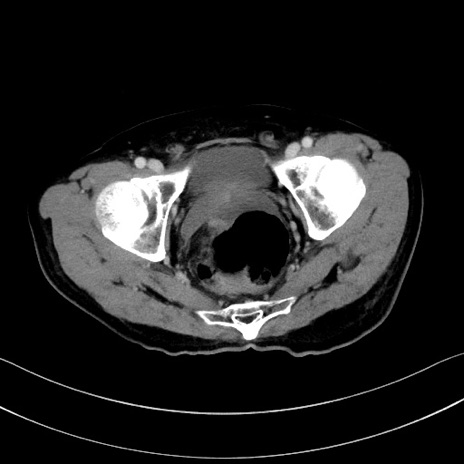

冠状断像

【症例】60歳代男性

【主訴】嘔吐

【現病歴】胃癌にて胃全摘後。食思不振が悪化し、夜中に嘔吐することがある。

【既往歴】胃癌、胃全摘、脾摘、胆摘後

【データ】WBC 5900、CRP 10.56